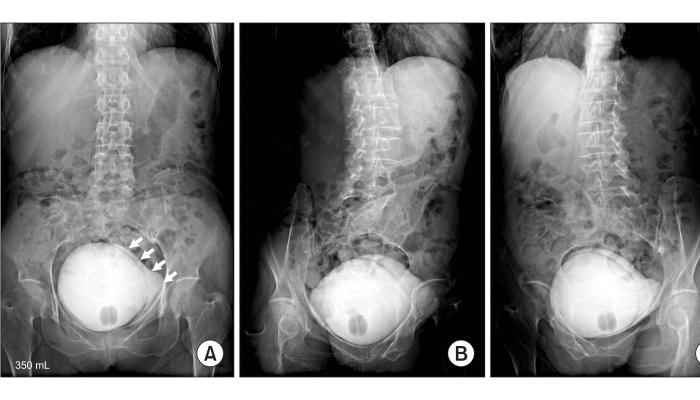

سیستواورتروگرام یا VCUG (Voiding Cysto Urethro Graphy) یکی از روشهای تصویربرداری پزشکی است که برای بررسی عملکرد مثانه و مجرای ادرار استفاده میشود. در این روش با کمک ماده حاجب و تصویربرداری با اشعه ایکس، وضعیت جریان ادرار و شکل دستگاه ادراری بهطور دقیق دیده میشود. پزشکان از VCUG برای تشخیص مشکلاتی مثل ریفلاکس ادراری (بازگشت ادرار به کلیهها)، تنگی یا انسداد مجرای ادرار و بررسی عوارض عفونتهای مکرر ادراری استفاده میکنند.

فرآیند انجام VCUG ساده است اما ممکن است برای بیمار کمی نگرانکننده به نظر برسد. در این روش ابتدا یک لوله باریک و استریل به نام سوند از طریق مجرای ادرار وارد مثانه میشود. سپس ماده حاجب (Contrast) از طریق این سوند وارد مثانه میشود تا در تصاویر اشعه ایکس بهخوبی دیده شود. وقتی مثانه پر شد، از بیمار خواسته میشود که ادرار کند. در همین زمان تصویربرداری انجام میشود تا جریان ادرار و حرکت ماده حاجب در دستگاه ادراری دیده شود.